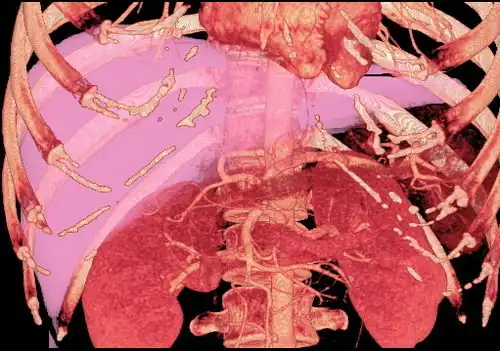

With the recent advances of noninvasive imaging, living liver donors usually have to undergo imaging examinations for liver anatomy to decide if the anatomy is feasible for donation. The evaluation is usually performed by multidetector row computed tomography (MDCT) and magnetic resonance imaging (MRI). MDCT is good in vascular anatomy and volumetry. MRI is used for biliary tree anatomy. Donors with very unusual vascular anatomy, which makes them unsuitable for donation, could be screened out to avoid unnecessary operations.

MDCT image. Arterial anatomy contraindicated for liver donation -

MDCT image. Portal venous anatomy contraindicated for liver donation -

MDCT image. 3D image created by MDCT can clearly visualize the liver, measure the liver volume, and plan the dissection plane to facilitate the liver transplantation procedure. -

Phase contrast CT image. Contrast is perfusing the right liver but not the left due to a left portal vein thrombus.